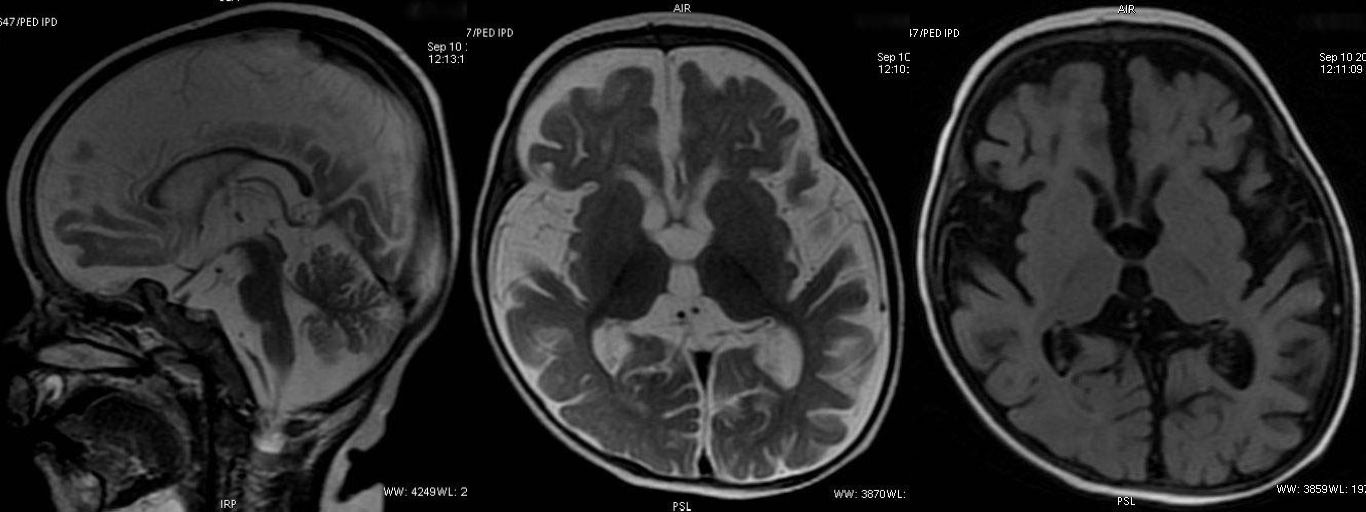

T2W sagittal, axial and axial FLAIR sequence showing significant diffuse atrophy and reduced volume of corpus callosum. No evidence of poor myelination appreciable.

Non specific cerebral atrophy of different grades was observed in all cases except one. In [Table/Fig-2], reduced thickness of corpus callosum was observed in six patients on MRI brain studies. ITS cases who had severe wasting, three out of four showed evidence of cerebral atrophy; all three children with moderate wasting had evidence of cerebral atrophy. Cerebral atrophy was observed in all children with stunting as well as in children having normal height for age and sex. Some patients (6/10) had mild to moderate ventricular dilatation and most patients (9/10) had prominence of Sylvian sulcus. Ventricular dilatation and prominence of Sylvian sulcus had correlation with the grades of cerebral atrophy in all cases [Table/Fig-3,4,5,6,7,8,9,10,11 and 12].